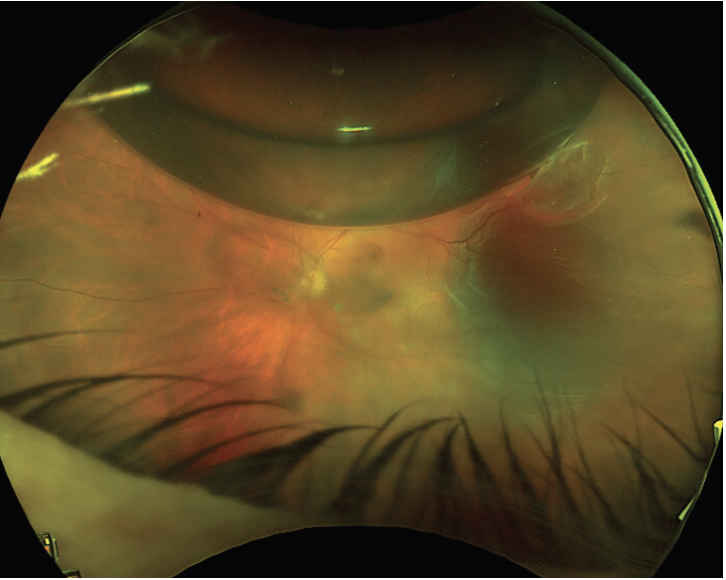

![]() |

| Figure 1. Recurrent retinal detachment caused by a new tear (2:00) in an eye with a previously well treated retinal detachment (with a break at 11:00). |

• New break development. Continued vitreous traction or vitreous contraction can lead to the development of new breaks (Figure 1).